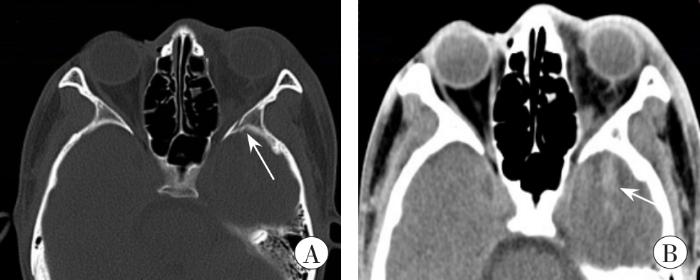

受伤当日头颅、眼眶CT示:左眼眶周软组织肿胀,左眼眶外侧壁近眶尖处骨折,左侧眶尖血肿,左颞叶条状高密度影,提示左颞叶脑挫裂伤(图3)。

受伤当日的头颅、眼眶CT图像

A:左眼眶外侧壁近眶尖处骨折(箭头所示);B:左颞叶脑挫裂伤(箭头所示)

CT images of head and orbit on the day of injury